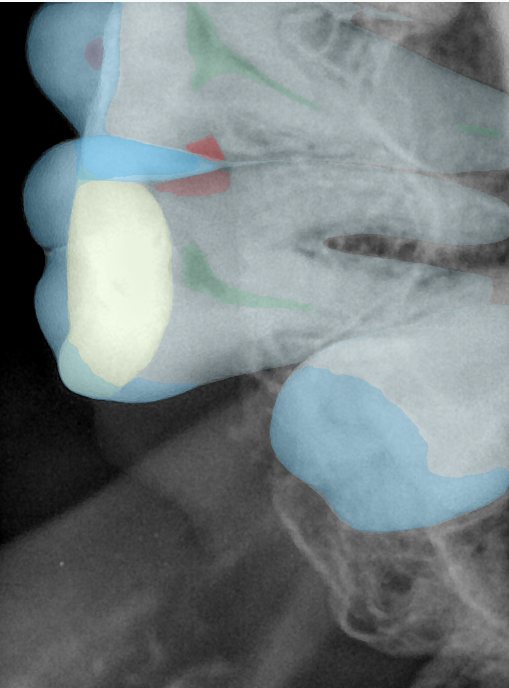

CR/DR 牙齿分割阶段记录

当前进展

- 完成了 CR/DR 牙齿相关分割训练

- 当前结果已经达到阶段预期,但仍有细节问题需要继续处理

相关测试

遇到的问题

- 训练过程中出现过 mask 下移问题

- 部分结果会出现 box 填充异常

- mask 边缘仍然有比较明显的锯齿感